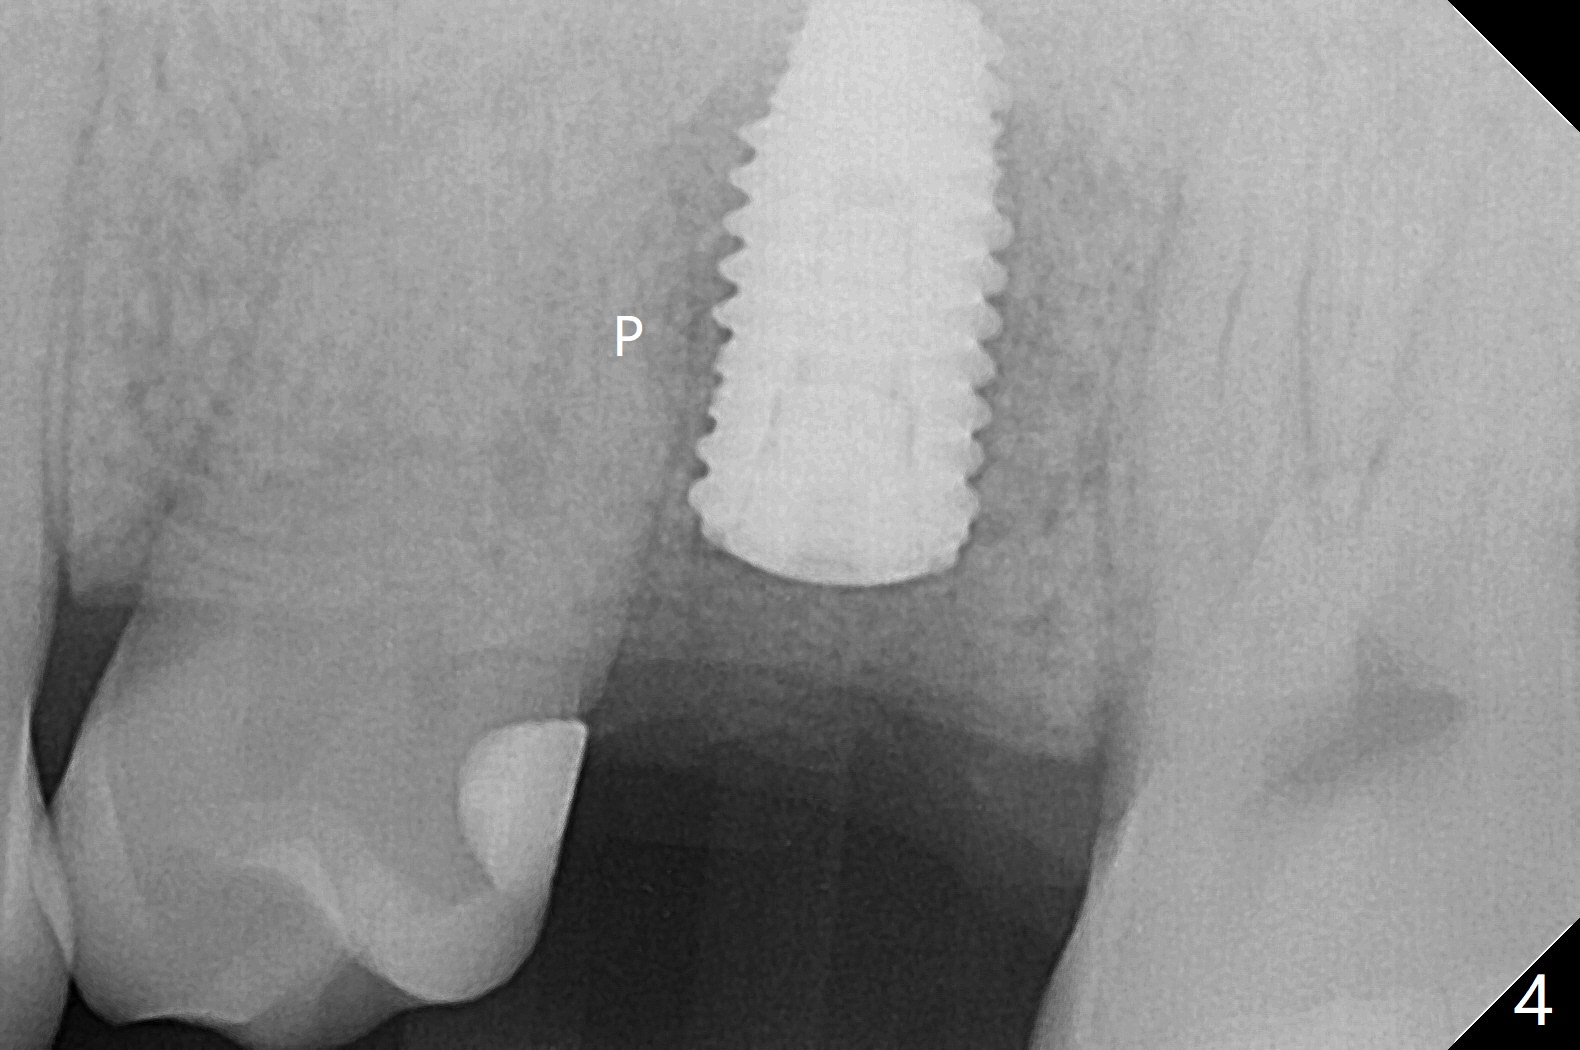

Low bone density is confirmed during osteotomy at #14 (6 months post socket preservation).  Underprep is adopted: after use of 3.5x10 mm drill instead of 4.5x10 mm one, a 4x10 and 4.5x10 mm dummy implant are placed for bone condensation.  When a 5x10 mm definitive implant is placed, it is unable to be placed to the depth.  After use of 4.0x10 mm, the final implant reaches depth ~ 1 mm more than planned.  But there appears no bone palatal to the implant clinically.  Small-field CT is taken.  In fact there is crestal bone palatal to the implant, but in small amount and in low bone density (Fig.1,2).  The implant should have been designed to be placed more buccal (Fig.3 arrow).  The implant also looks to be placed too close the root of the tooth #13, probably related to the rotation of #13 (Fig.4).  Unfortunately the patient does not agree to have limited orthodontics.  After palatal bone graft, GEM Cap is used to close the access with periodontal glue (Fig.5).  Spacer/periodontal dressing should have been used.  The wound heals 8 months postop, but 2-3 palatal threads are exposed with uncover.  After 6 mm profile drill and placement of a 6x4 mm healing abutment, allograft is placed palatal (Fig.6).  Upper Molar Immediate Implant, Trajectory II Shield Next Case of Buccal Defect  SP Xin Wei, DDS, PhD, MS 1st edition 11/19/2019, last revision 09/19/2020